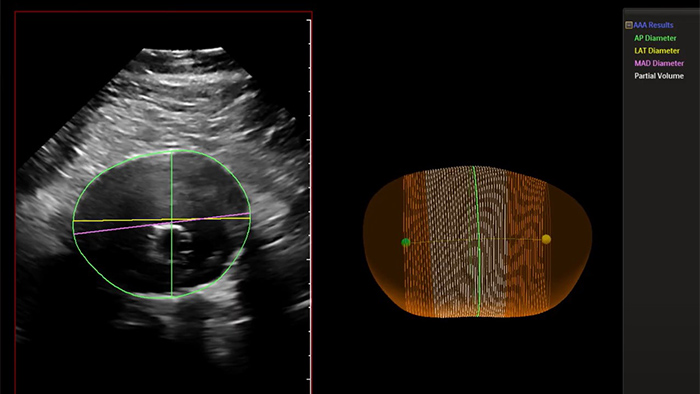

Abdominal aortic thumbnail

Philips Abdominal Aortic Aneurysm Model

Philips AAA Model is a software application that helps clinicians detect, segment and quantify 3D ultrasound data for use in surveillance of native and post-endovascular aneurysm repair (EVAR) AAAs.